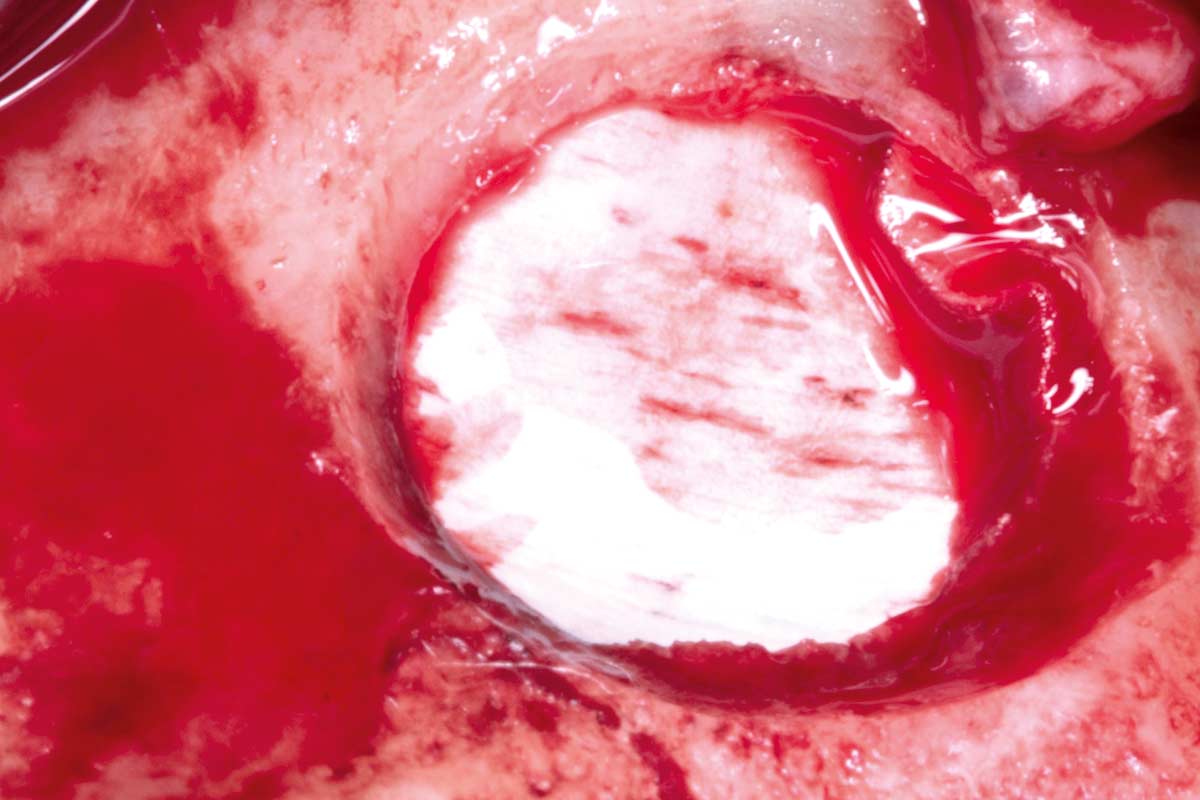

21/35 - Bone augmentation using cerabone®, maxgraft®, and autologous boneMaxillary sinus cyst removal using the Crocodile Technique and subsequent lateral sinus lift - Dres. C. Scognamiglio and A. Perucchi